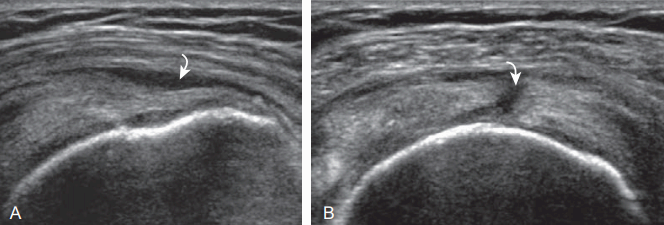

가시위근힘줄의 부분 찢어짐(partial thickness tear)은 힘줄에 부분적 비정상소견을 보이는데, 경계가 좋은 낮은 에코 또는 에코 없는 병변으로 보인다. 관절 쪽 힘줄의 부분 째짐은 주로 앞쪽 먼 쪽에서 큰 거친 면 가까이에서 발생한다. 높은 에코와 낮은 에코가 섞인 모양으로 보일 수도 있는데, 이는 높은 에코의 힘줄이 찢어지고, 찢어진 곳에는 낮은 에코의 액체가 고이기 때문이다. 찢어진 힘줄에 바로 가까이 있는 큰 거친 면 뼈겉질이 흔히 불규칙해 보이는데 이것이 만성적으로 힘줄 째짐에 기여(attribution)했다고 보인다. 흔하지는 않지만 몸 쪽(근위부)에서 힘줄이 찢어지거나, 이전에는 정상이었던 힘줄의 급성 째짐에서는 뼈겉질의 불규칙이 없다. 관절 쪽 부분 째짐에서는 힘줄의 윤활주머니 쪽 가장자리가 볼록한 모양을 유지하고 있는데, 이는 힘줄전체의 크기가 줄어들지 않았기 때문이다. 힘줄의 찢어진 끝이 낮은 에코의 관절연골과 직접 닿아 있을 수도 있다. 힘줄의 찢어진 부분에서 낮은 에코로 보이는 관절연골의 표면이 높은 에코의 줄(line)로 보일 수 있는데, 이를 연골접촉면증후(cartilage interface sign)이라고 한다. 힘줄-뼈 접촉면 또는 부착부 찢어짐(rim-rent tear)은 큰 거친 면 바로 가까이의 힘줄끝에서 관절 쪽 부분 째짐이 생긴 것을 말한다.

supraspinatus : partial -thickness tear ( A:long axis B: short axis) 윤활주머니 쪽 부분째짐의 초음파소견은 기본적으로 관절 쪽 부분 째짐과 같고, 다만 손상 부위가 윤활주머니 쪽이라는 것이다. 힘줄이 윤활주머니 쪽에서 찢어져서 큰 거친 면으로 확장된 경우라도 관절 쪽 힘줄 손상이 없다면 윤활주머니 쪽 부분 째짐이다. 이때, 정상 힘줄의 볼록한 모양이 없어지기도 하고, 찢어진 힘줄 부위에 세모근과 활액낭이 움푹 내려앉은(함몰된) 것처럼 보인다. 역시 큰 거친 면 뼈겉질이 불규칙하게 보이는 것이 보통이다. 활액낭염의 윤활염증 조직이 같은 에코의 힘줄 째진 곳에 놓여서 힘줄 째짐과 가늘어짐이 뚜렷하지 않을 수 있다.